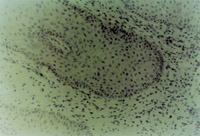

MEBTÒ½ÖÎ20Ì죬Éî¶È´´Ãæ´¦×éÖ¯ÇÐÆ¬¿É¼ûÐÂÉú½ÏÆëÈ«µÄ¸´²ãÁÛ×´ÉÏÆ¤×éÖ¯£¬±íƤ²ãϸ°û״̬ÒѾ­Ç÷ÓÚÕý³££¬ÕæÆ¤²ã½ºÔ­ÏËάϸ°ûºÍ΢Ѫ¹Ü״̬ÒѾ­³öÏÖ¡£

Ò½ÖÎ30Ììºó£¬´´ÃæÉÏÆ¤×éÖ¯ÔÙÉú½¨¸´ÓÅÁ¼£¨Í¼5-3-5£©£¬Æ¤·ô½á¹¹ÒѾ­¸ù»ùÕý³££¨Í¼5-3-6£©¡£

5-3-5 MEBT/MEBOÒ½ÖÎ30Ì죬´´ÃæÆ¤·ôÔÙÉú½¨¸´ÓÅÁ¼

5-3-6 Ò½ÖÎ30ÌìºóµÄ´´ÃæÆä±íƤ×éÖ¯£¬ÕæÆ¤×éÖ¯½á¹¹ÒѳÊÉúÀí״̬  HE¡Á20